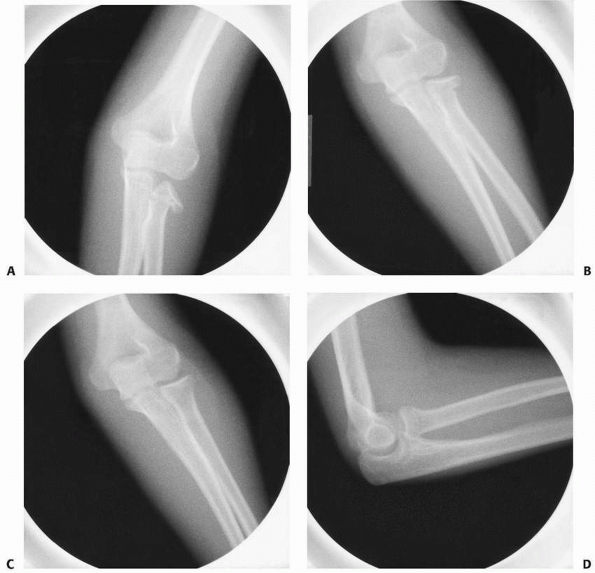

![]() |

FIGURE 11-4 A,B. AP and lateral radiographs demonstrating a radial neck fracture in a patient with a nonossified proximal radial epiphysis. C. Arthrogram prior to reduction demonstrating location/displacement of nonossified proximal radial epiphysis. D-F.

Arthrogram/radiographs after reduction with intramedullary technique. (From Javed A, Guichet J.M. Arthrography for reduction of a fracture of the radial neck in a child with a nonossified radial epiphysis. J Bone Joint Surg Br 2001;83-B:542-543, with permission.) |